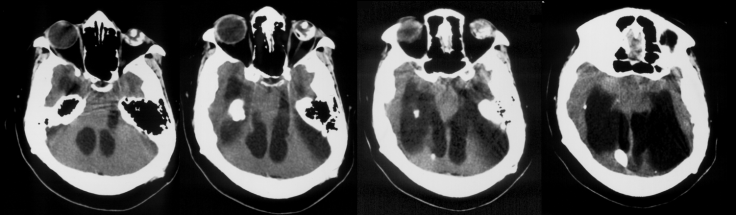

l’engagement temporal

il traduit la compression :

- du système d’éveil (réticulée activatrice ascendante du mésencéphale et diéncéphale)

- du mésencéphale et du noyau du III

- de la voie pyramidale

en conséquence, il se manifeste par :

- des troubles de conscience

- une mydriase homolatérale

- un déficit ou réaction de décérébration ou déficit contro-latéral

il provoque en outre une compression de l’artère cérébrale postérieure contre le bord libre de la tente du cervelet, à l’origine d’une ischémie (cf. ci-contre) avec comme conséquence une hémianopsie latérale homonyme.